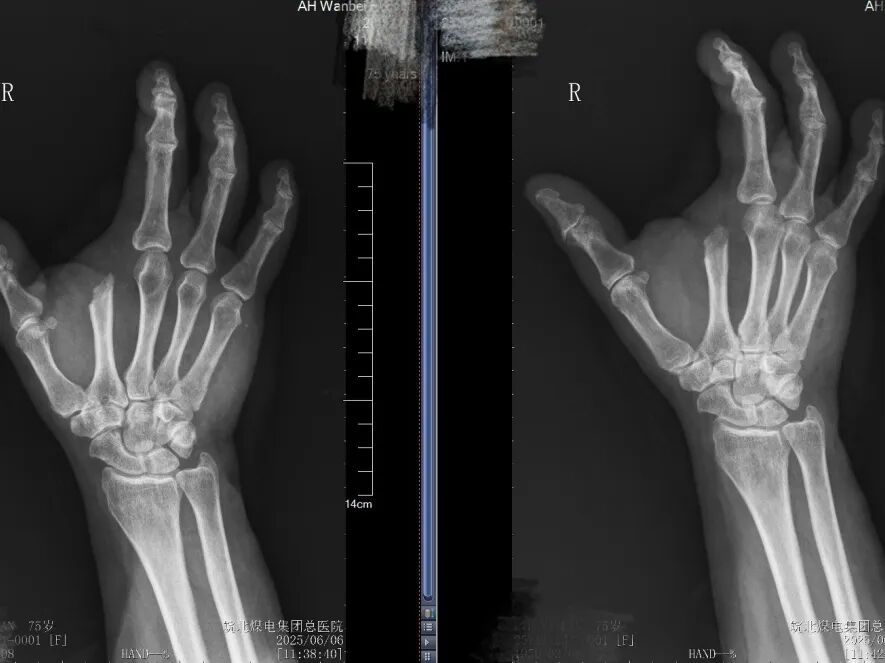

家人将其急诊送到皖北煤电集团总医院时,刘奶奶的右手已惨不忍睹:食指粉碎性骨折、手背皮肤像破布条一样撕脱,肌腱骨头裸露,污染严重的创面让感染风险激增!

面对如此复杂的毁损伤,张文龙副主任医师及杨西洲主治医生及手足外科专家团队迅速评估:患者高龄、组织缺损严重、血管神经损伤及感染风险极高,手术既要彻底清创、精准修复,又要最大限度保留手部功能。

手术室内,无影灯将术野照得通明。张文龙副主任医师和杨西洲医师默契配合,在显微器械下精细的清楚坏死组织,随后,张主任仔细测量评估创面后,从残端精心设计切取一块大小适宜的皮瓣,在保持供血完整的前提下,将其移植至虎口缺损处,重建拇指对掌功能。手术顺利完成。